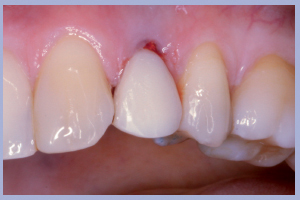

- Figg. 15a, b – Inserimento e preparazione del moncone temporaneo di destra

- Figg. 16a, b – Consegna della corona provvisoria in resina di destra

- Figg. 17a, b – Inserimento e preparazione del moncone temporaneo di sinistra

- Fig. 18 – Consegna della corona provvisoria in resina di sinistra

- Fig. 19 – Visione d’insieme al termine dell’intervento

- Figg. 20a, b, c – Controllo clinico e radiologico a 2 settimane dall’intervento